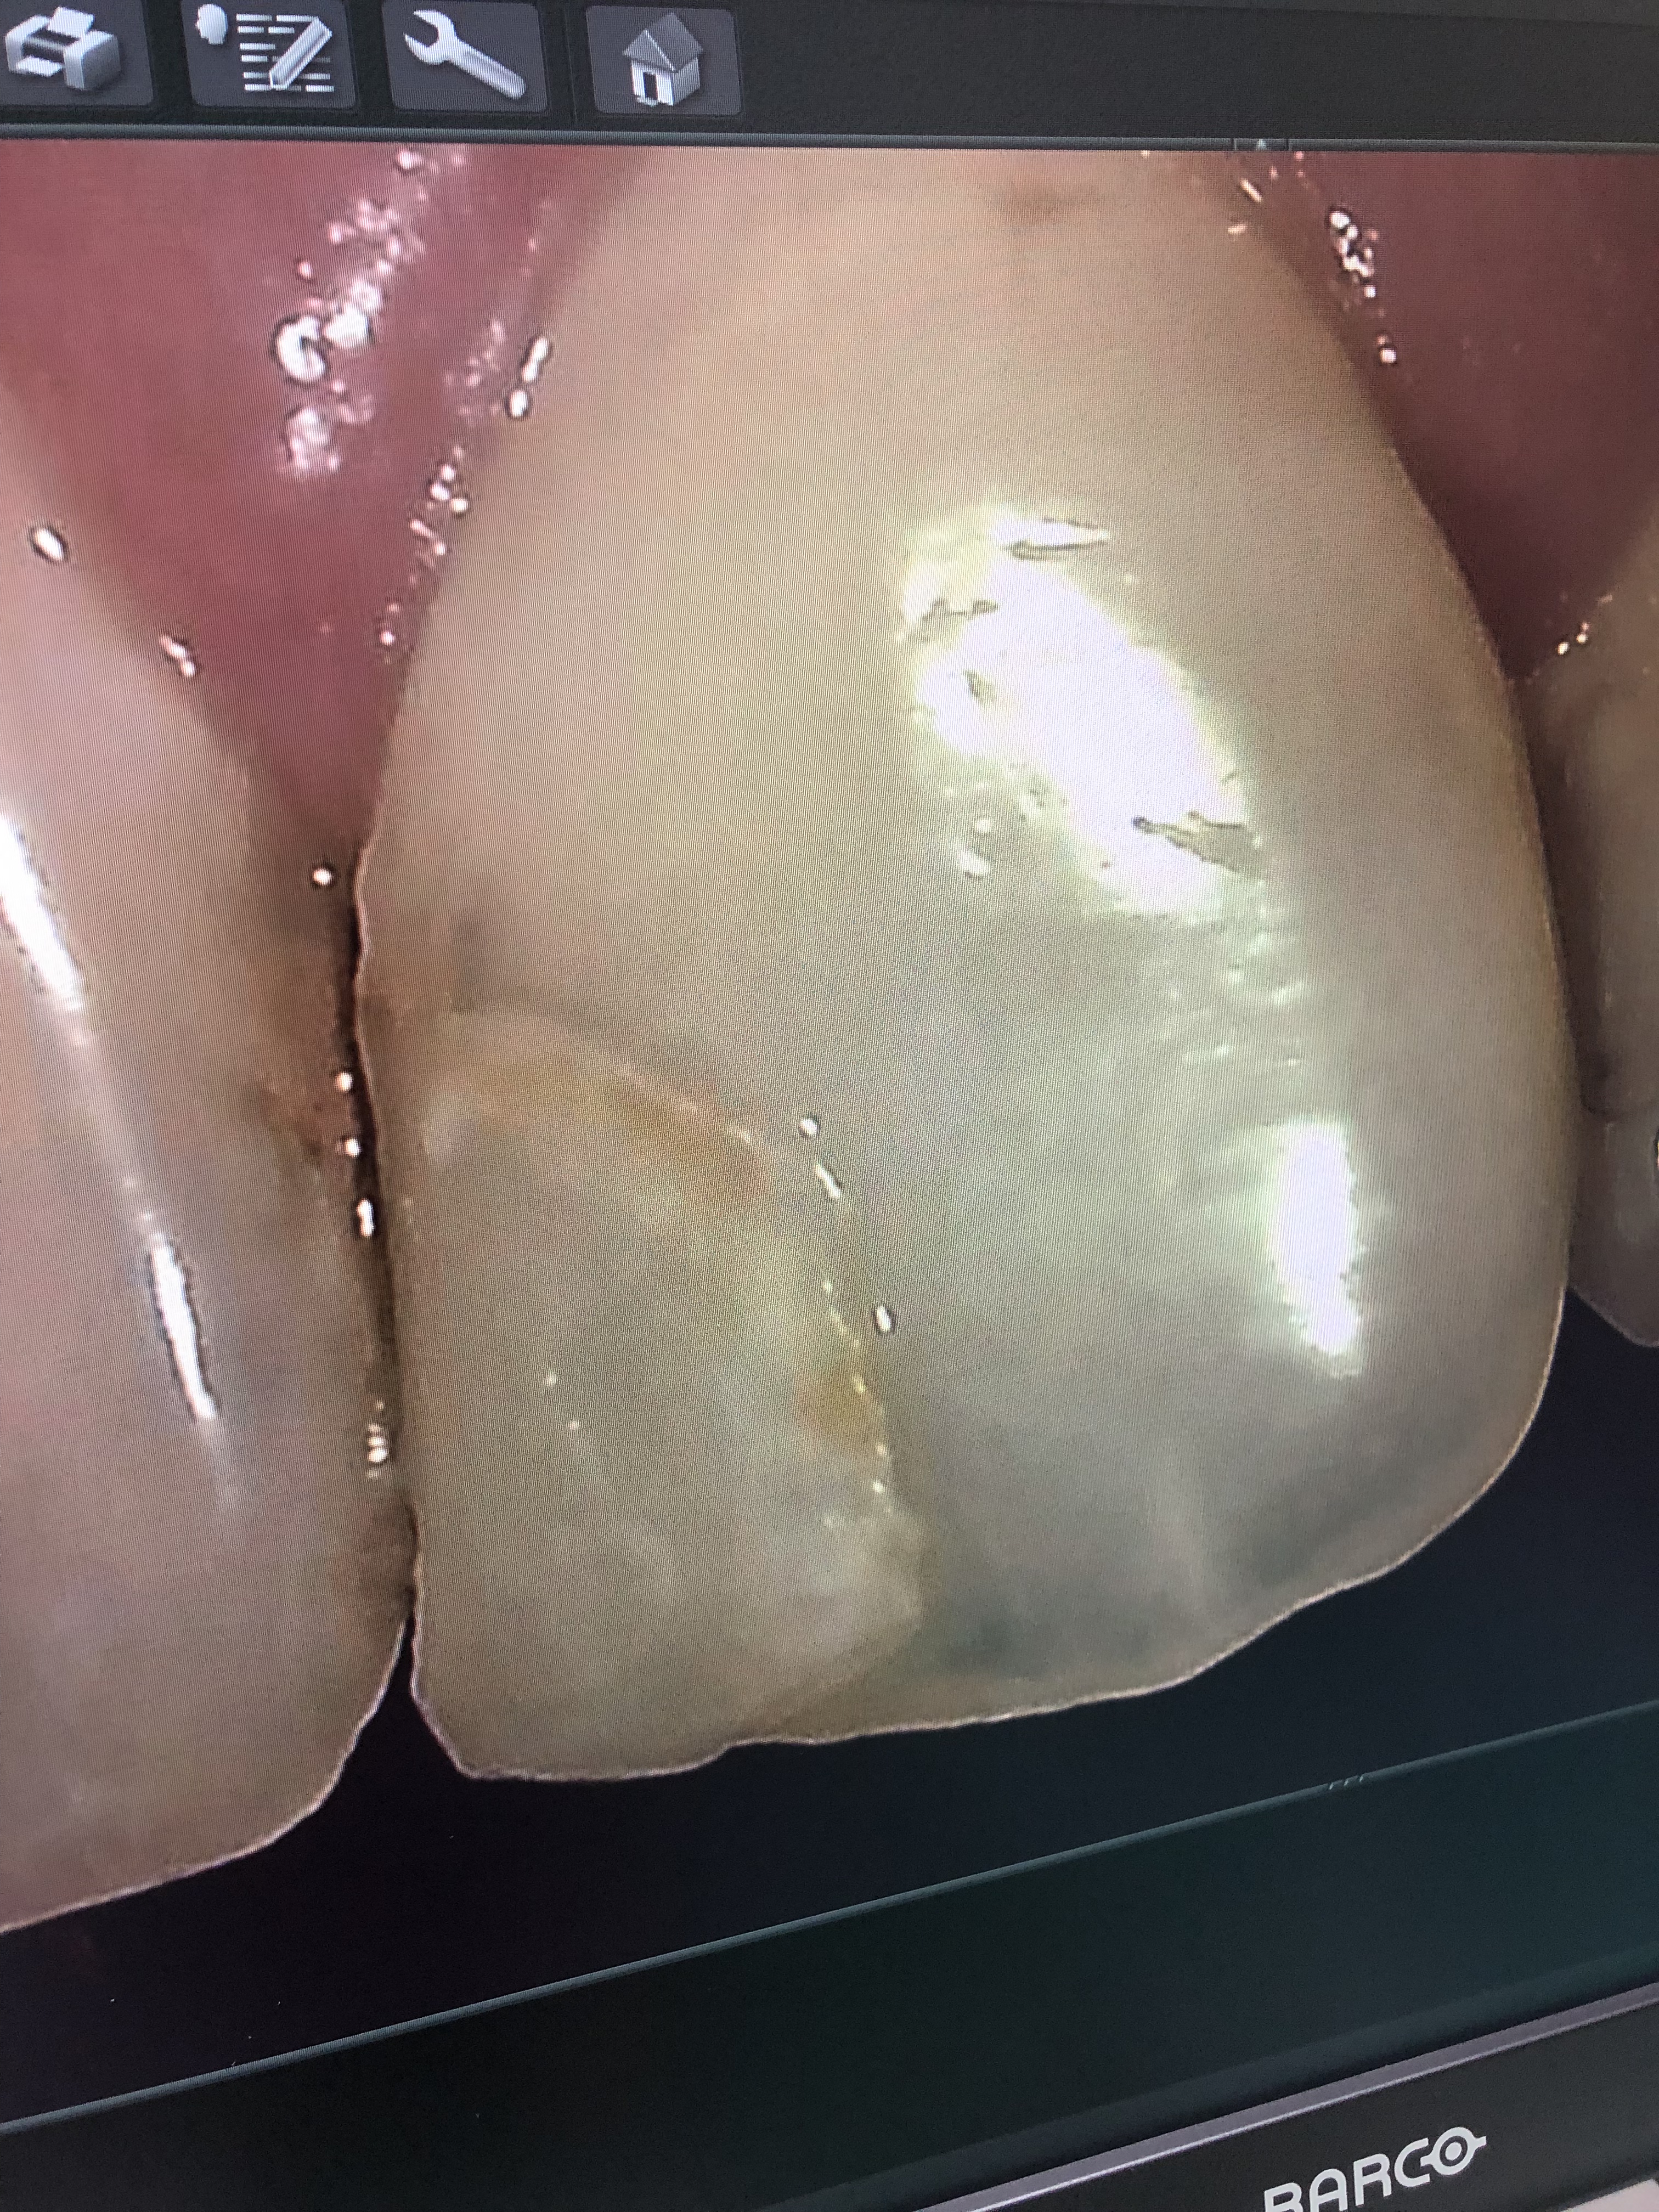

その中でも、オムニクロマと言うコンポジット充填剤が今使われてきています。

オムニクロマ充填剤は、歯の色と同化する性質を持った充填剤です。

今までの充填剤は、何種類かの色を選んで充填していましたが、オムニクロマは色が歯の色と同化してしまうので色を選ぶ必要がないのです。

前歯部や臼歯部にも使用でき、詰め物しているのがわからないくらいです。